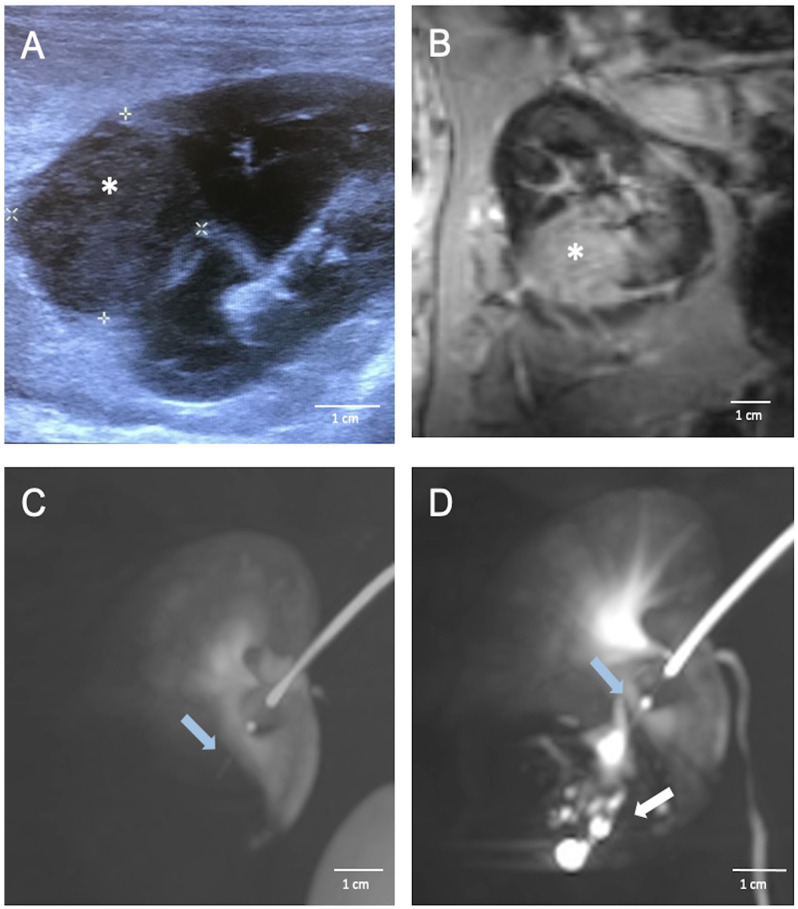

{"title":"VX2 兔子模型中的跨血管壁细胞移植、移植物和肿瘤通路。","authors":"Victoria Lövljung, Mathias Waldén, Mikael Sandell, Peter Damberg, Staffan Holmin, Fabian Arnberg Sandor","doi":"10.1177/09636897251313678","DOIUrl":null,"url":null,"abstract":"<p><p>The trans-vessel wall device (TW-device) is a new endovascular tool for precise and safe delivery of various payloads (cells, viral, modified RNA, chemotherapy, growth factors) in oncology and regenerative medicine. The twofold aim of this study was to assess cell engraftment and tumor growth using the TW-device for endovascular transplantation and to evaluate its ability to directly access solid tumors. We used the VX2 model in the rabbit kidney to compare percutaneously implanted fresh VX2 cells with TW-device injections of cryopreserved VX2 cells. We demonstrated the feasibility of endovascular transplantation (<i>n</i> = 7) of tumor cells, achieving a 57.1% engraftment rate despite cryopreservation, comparable with 70% for percutaneous delivery of fresh cells (<i>n</i> = 10). Re-access using the TW-device was 100% successful (<i>n</i> = 11) with super-selective intratumoral contrast administration without complications. In conclusion, endovascular transplantation of VX2 cells using the TW-device resulted in proliferating cell grafts in the rabbit kidney establishing functional proof that cells indeed survive handling, preparation, and device passage. We also show the TW-device is able to access solid tumor parenchyma allowing precise intraparenchymal administration.This proof-of-concept study open up possibilities for repeated direct parenchymal injections via the endovascular route in any hard to reach organ.</p>","PeriodicalId":9721,"journal":{"name":"Cell Transplantation","volume":"34 ","pages":"9636897251313678"},"PeriodicalIF":3.2000,"publicationDate":"2025-01-01","publicationTypes":"Journal Article","fieldsOfStudy":null,"isOpenAccess":false,"openAccessPdf":"https://www.ncbi.nlm.nih.gov/pmc/articles/PMC11773539/pdf/","citationCount":"0","resultStr":"{\"title\":\"Trans-Vessel Wall Cell Transplantation, Engraftment, and Tumor Access in the VX2 Rabbit Model.\",\"authors\":\"Victoria Lövljung, Mathias Waldén, Mikael Sandell, Peter Damberg, Staffan Holmin, Fabian Arnberg Sandor\",\"doi\":\"10.1177/09636897251313678\",\"DOIUrl\":null,\"url\":null,\"abstract\":\"<p><p>The trans-vessel wall device (TW-device) is a new endovascular tool for precise and safe delivery of various payloads (cells, viral, modified RNA, chemotherapy, growth factors) in oncology and regenerative medicine. The twofold aim of this study was to assess cell engraftment and tumor growth using the TW-device for endovascular transplantation and to evaluate its ability to directly access solid tumors. We used the VX2 model in the rabbit kidney to compare percutaneously implanted fresh VX2 cells with TW-device injections of cryopreserved VX2 cells. We demonstrated the feasibility of endovascular transplantation (<i>n</i> = 7) of tumor cells, achieving a 57.1% engraftment rate despite cryopreservation, comparable with 70% for percutaneous delivery of fresh cells (<i>n</i> = 10). Re-access using the TW-device was 100% successful (<i>n</i> = 11) with super-selective intratumoral contrast administration without complications. In conclusion, endovascular transplantation of VX2 cells using the TW-device resulted in proliferating cell grafts in the rabbit kidney establishing functional proof that cells indeed survive handling, preparation, and device passage. We also show the TW-device is able to access solid tumor parenchyma allowing precise intraparenchymal administration.This proof-of-concept study open up possibilities for repeated direct parenchymal injections via the endovascular route in any hard to reach organ.</p>\",\"PeriodicalId\":9721,\"journal\":{\"name\":\"Cell Transplantation\",\"volume\":\"34 \",\"pages\":\"9636897251313678\"},\"PeriodicalIF\":3.2000,\"publicationDate\":\"2025-01-01\",\"publicationTypes\":\"Journal Article\",\"fieldsOfStudy\":null,\"isOpenAccess\":false,\"openAccessPdf\":\"https://www.ncbi.nlm.nih.gov/pmc/articles/PMC11773539/pdf/\",\"citationCount\":\"0\",\"resultStr\":null,\"platform\":\"Semanticscholar\",\"paperid\":null,\"PeriodicalName\":\"Cell Transplantation\",\"FirstCategoryId\":\"3\",\"ListUrlMain\":\"https://doi.org/10.1177/09636897251313678\",\"RegionNum\":4,\"RegionCategory\":\"医学\",\"ArticlePicture\":[],\"TitleCN\":null,\"AbstractTextCN\":null,\"PMCID\":null,\"EPubDate\":\"\",\"PubModel\":\"\",\"JCR\":\"Q3\",\"JCRName\":\"CELL & TISSUE ENGINEERING\",\"Score\":null,\"Total\":0}","platform":"Semanticscholar","paperid":null,"PeriodicalName":"Cell Transplantation","FirstCategoryId":"3","ListUrlMain":"https://doi.org/10.1177/09636897251313678","RegionNum":4,"RegionCategory":"医学","ArticlePicture":[],"TitleCN":null,"AbstractTextCN":null,"PMCID":null,"EPubDate":"","PubModel":"","JCR":"Q3","JCRName":"CELL & TISSUE ENGINEERING","Score":null,"Total":0}

跨血管壁装置(tr -device)是一种新的血管内工具,用于肿瘤和再生医学中各种有效载荷(细胞,病毒,修饰RNA,化疗,生长因子)的精确和安全输送。本研究的双重目的是评估使用tw -装置进行血管内移植的细胞植入和肿瘤生长,并评估其直接接触实体瘤的能力。我们使用兔肾VX2模型,比较经皮植入新鲜VX2细胞与tw装置注射冷冻保存的VX2细胞。我们证明了肿瘤细胞血管内移植(n = 7)的可行性,尽管冷冻保存,植入率仍为57.1%,而经皮输送新鲜细胞的植入率为70% (n = 10)。使用tw -装置重新进入的成功率为100% (n = 11),超选择性肿瘤内造影剂施用无并发症。综上所述,使用TW-device对VX2细胞进行血管内移植,在兔肾中产生了增殖的细胞移植物,证明了细胞在处理、制备和设备传递过程中确实存活了下来。我们也展示了tw -装置能够进入实体瘤实质,允许精确的实质内给药。这一概念验证研究开辟了通过血管内途径在任何难以到达的器官中重复直接实质注射的可能性。

The trans-vessel wall device (TW-device) is a new endovascular tool for precise and safe delivery of various payloads (cells, viral, modified RNA, chemotherapy, growth factors) in oncology and regenerative medicine. The twofold aim of this study was to assess cell engraftment and tumor growth using the TW-device for endovascular transplantation and to evaluate its ability to directly access solid tumors. We used the VX2 model in the rabbit kidney to compare percutaneously implanted fresh VX2 cells with TW-device injections of cryopreserved VX2 cells. We demonstrated the feasibility of endovascular transplantation (n = 7) of tumor cells, achieving a 57.1% engraftment rate despite cryopreservation, comparable with 70% for percutaneous delivery of fresh cells (n = 10). Re-access using the TW-device was 100% successful (n = 11) with super-selective intratumoral contrast administration without complications. In conclusion, endovascular transplantation of VX2 cells using the TW-device resulted in proliferating cell grafts in the rabbit kidney establishing functional proof that cells indeed survive handling, preparation, and device passage. We also show the TW-device is able to access solid tumor parenchyma allowing precise intraparenchymal administration.This proof-of-concept study open up possibilities for repeated direct parenchymal injections via the endovascular route in any hard to reach organ.